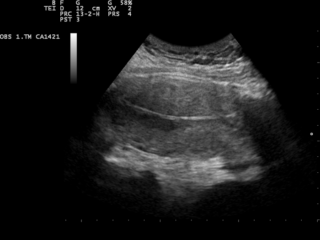

Contrairement à la radiologie, l’échographie n’utilise pas les rayons X, mais les ultrasons. Le technicien va enduire la zone à examiner de gel, puis passer une sonde dessus, émettant et recevant des ultrasons. Le gel est utilisé pour atténuer la fine couche d’air entre la peau et la sonde, qui peut entraver la visibilité.

Pendant l’examen, la sonde est reliée à un moniteur qui permet de voir l’image se former. Il revient au technicien de balayer la zone pour obtenir une vision complète des organes à examiner. L’échographie permet alors d’avoir une vision précise des organes sans utiliser de rayons X, c’est pourquoi cette méthode est privilégiée lors des suivis de grossesse.